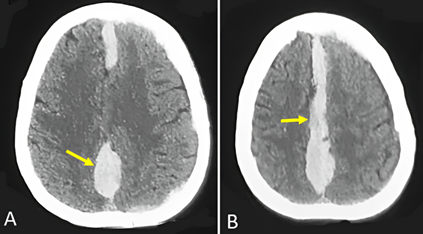

We report a 55-years-old woman presented with consciousness disorder with vomiting for 2 days. Past history revealed a mitral replacement in 2008 and she had beeing using anticoagulant agent (Acenocoumarol). The neurologic examination revealed a disorder of consciousness was 07/15 assessed by the Glasgow Coma Scale (GCS), pupil in myosis, stiff neck. The biological check-up showed a platelet count was 219,000/mm3, and thrombo test was 55% and an International Normalized Ratio of 1.39. CT (computed tomography) scan of the head showed a left subacute subdural hemispheric hematoma compressive with subfalcoral engagement associated with an acute ISDH (Figure 1). Consequently, we proceeded with the surgical evacuation of the left subdural hematoma via two burr-hole fronto-parietal craniotomy then she was transferred to the intensive careunit. The anticoagulant agent was stopped. The patient is still intubated, the sedation was stopped 3 days postoperatively with no sign of awakening. A control CT scan was performed three days after, showing only the acute IHSDH (Figure 2).

Figure 2: A and B: CT-scan of the head three days postoperatively showing only acute IHSDH without HSDH (arrow).